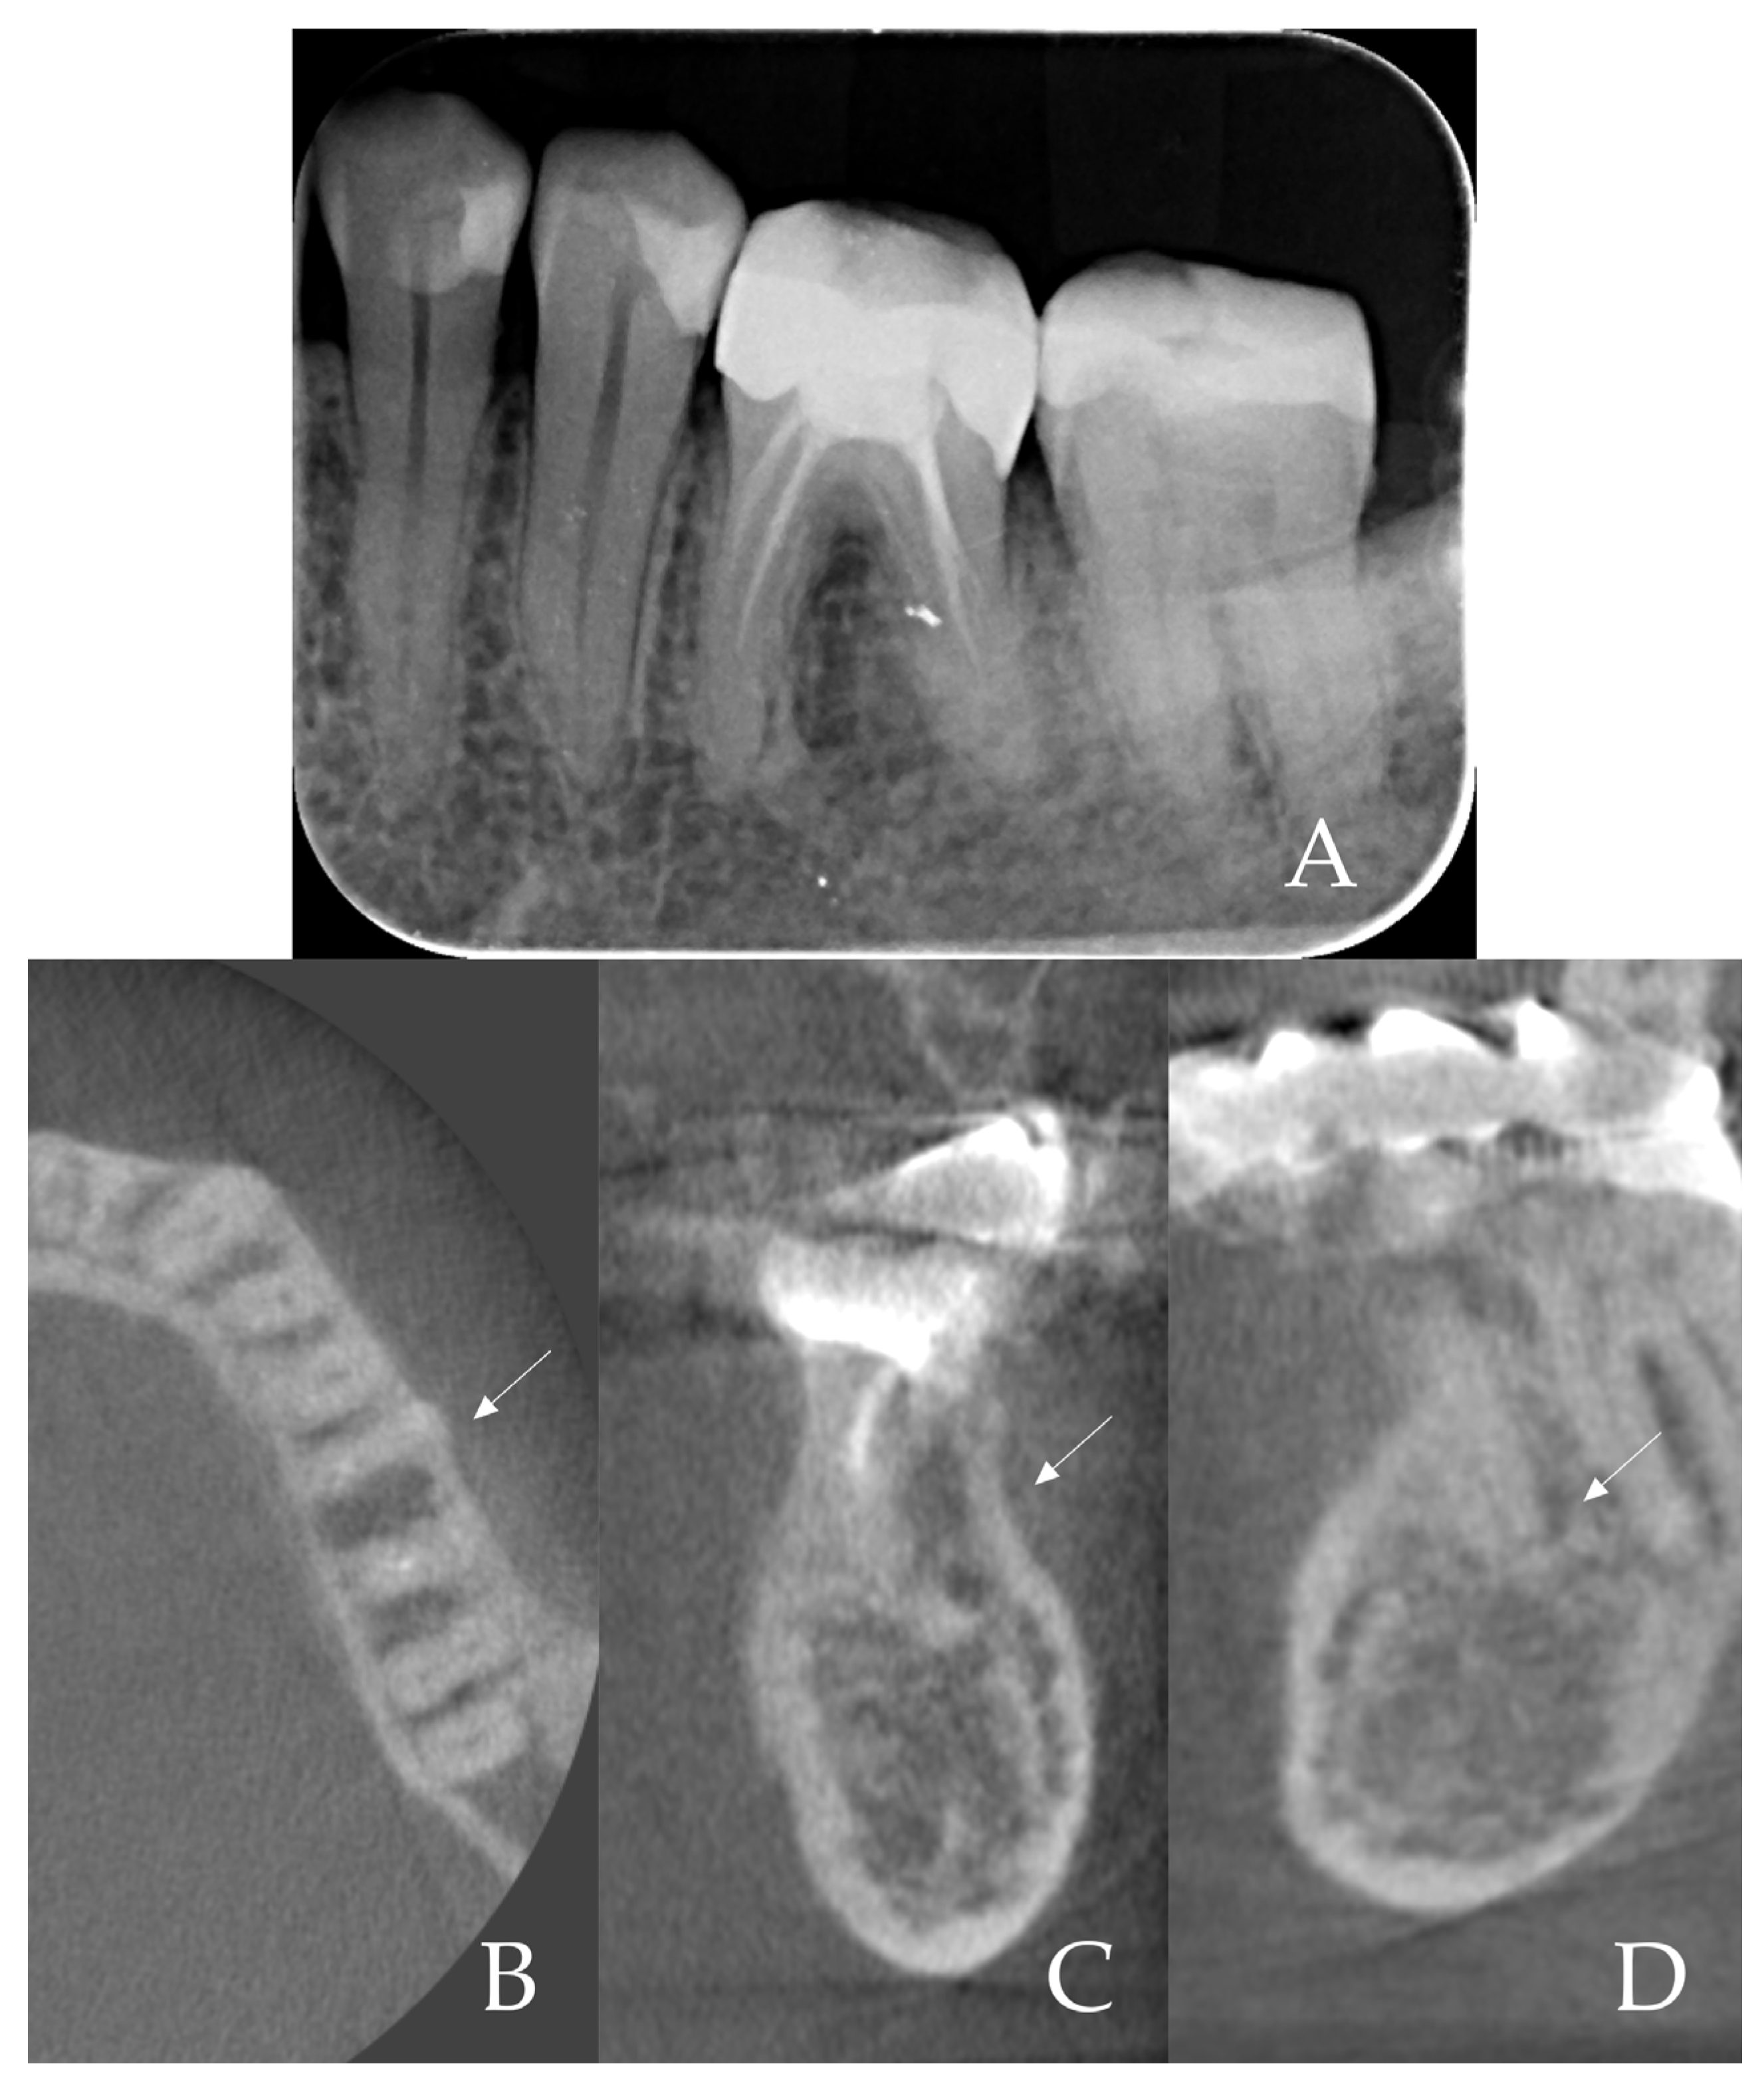

- Root sectioning: After performing mandibular nerve block anesthesia, the crown of tooth #36 (Figure 2A) was removed (decoronation was performed) (Figure 2B). The mesial and distal roots were then separated buccolingually using a long-shanked, straight diamond bur in a high-speed handpiece with copious irrigation (Figure 2C). The preoperative CBCT was consulted to guide the depth and orientation of the cuts, accounting for the roots’ length, curvature, and angulation.

- Partial root extraction: Each root was sectioned in a mesiodistal direction approximately 1–1.5 mm buccally from the center of each root surface to a depth of about two-thirds of the root length, using a #2 long cylinder bur from Gluckman’s partial extraction therapy (PET) surgical kit (Megagen, Seoul, South Korea). This created buccal and lingual segments for each root. The lingual root segments (along with their apices) were carefully extracted, leaving only the buccal portions of the roots in place as the “socket shields” (Figure 2D). If the lingual part fails to extract and remains in the socket still attached to the shield, it should be detached from the shield with bur #3 and extracted in the conventional way. In such cases, the bony septum can be drilled in the center to facilitate extraction.

- Implant osteotomy preparation: An implant osteotomy was created in the inter-radicular septum (furcation bone) of the extraction site [16]. Sequential drilling (using the standard Blue Diamond implant drill kit to the 4.3 mm diameter, Megagen, South Korea) was performed. Care was taken to angle the drills to stay in the middle of the socket and avoid encroaching on the buccal or lingual plates. The osteotomy was prepared to a depth such that the future implant platform would be positioned about 5–6 mm apical to the original buccal gingival margin (as estimated from the CBCT and clinical measurements). This depth was planned to place the implant platform approximately 3–4 mm below the alveolar crest and ~6 mm below the gingival margin once the implant was in place (accounting for the soft tissue height).

- Immediate post-op imaging: A postoperative CBCT scan was obtained to evaluate the implant position and to measure the alveolar ridge dimensions after implant placement (Figure 6). CBCT confirmed that the implant was accurately centered in the socket.